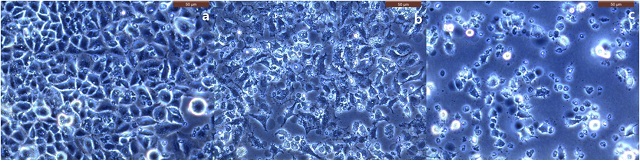

▲ (A)배양된 폐암세포, Cu-67 투여 전 광학영상, (B)사멸된 폐암세포 (20%), Cu-67 투여 후 8시간 경과, (C)사멸된 폐암세포 (80%) Cu-67 투여 후 24시간 경과 (사진 : 한국원자력연구원)

Cu-67은 이런 우수성에도 불구하고, 생산공정이 몹시 까다롭고 비용이 많이 들어 국내에서는 지금껏 생산하지 못했다. 원자력연구원은 이번에 자체 기술로 Cu-67을 생산하는데 성공했을 뿐 아니라 생산한 동위원소의 암세포 사멸효과도 입증했다.